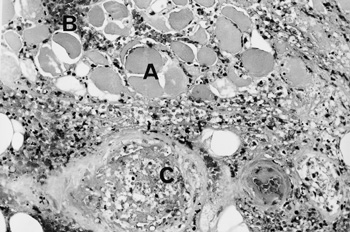

Investigations showed an elevated white cell count of 16 x 109/L (NR, 4.0–11.0 x 109/L), a platelet count of 432 x 109/L (NR, 150–400 x 109/L), an erythrocyte sedimentation rate of 110 mm/h (NR, 7–18 mm/h) and a C-reactive protein level of 119.3 mg/L (NR, 1.6–8.7 mg/L). Creatine kinase (174 U/L; NR, < 215 U/L) and lactate (0.6 mmol/L; NR, 0.5–2.0 mmol/L) levels were normal. Separate to the swelling on the medial aspect of the thigh, a presumed thrombus was palpable in the lateral accessory long saphenous vein. A subsequent ultrasound detected this thrombus extending from the mid thigh to the lateral aspect of the knee, but no deep venous thrombosis was found. She was treated with cephalexin and aspirin. Over the next two weeks, the thigh swelling evolved into a tender, palpable mass measuring 6 x 20 cm. A computed tomography (CT) scan revealed marked swelling of the entire adductor muscle group, but no discrete mass (Figure 1). In the absence of a clear diagnosis, an exploratory operation of her right thigh was performed. This showed no haemorrhage or abscess, but evidence of extensive oedema and necrosis of the adductor muscles. Samples taken for microbiological analysis were sterile. Histological examination of a biopsy specimen showed necrotic muscle, an inflammatory cell infiltrate, fibrosis and evidence of muscle fibre regeneration. The occasional small blood vessel containing fibrin thrombus was also seen, but no features of vasculitis were identified (Figures 2 and 3). A diagnosis of diabetic muscle infarction was made. ![]() ![]() Photomicrographs (original magnification x 250) of a biopsy specimen of the adductor group of muscles. Figure 2: Longitudinal section, showing necrotic muscle fibres (A) and granulomatous tissue (B). Figure 3: Cross-section showing necrotic muscle (A), an inflammatory cell infiltrate (B) and a blood vessel containing a thrombus (C). No evidence of vasculitis was seen. |